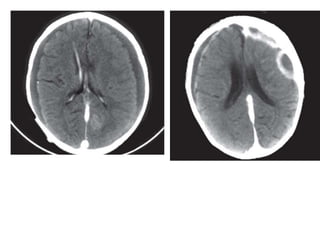

CECT axial scans of the cranium showing a large ring

enhancing lesion with smooth thin walls in a left parafalcine location with

extensive vasogenic edema causing effacement of the ipsilateral frontal

horn and midline shift to the contralateral side. Adjacent smaller enhancing

rings are also seen in another case—brain abscess with daughter

abscesses